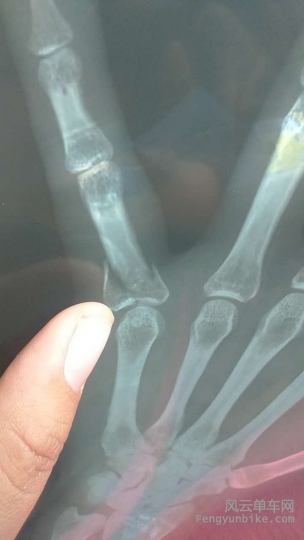

第二天,miya的报告也出来了,左小指骨穿插,骨折,再加右膝外伤。在把积水潭骨科主治大夫他们家的猪杀了之后,miya顺便用照片引爆了朋友圈。这可是900多粉丝的女神啊,刷评论都3-43-4篇的。

102.jpg